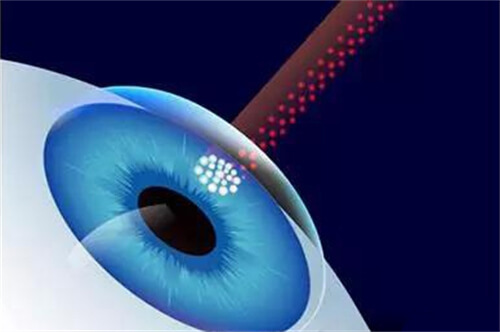

白内障手术是一种非常常见且安心的眼科手术,通常采用超声乳化技术将模糊的晶状体取出,然后植入人工晶状体以改善眼部视力。